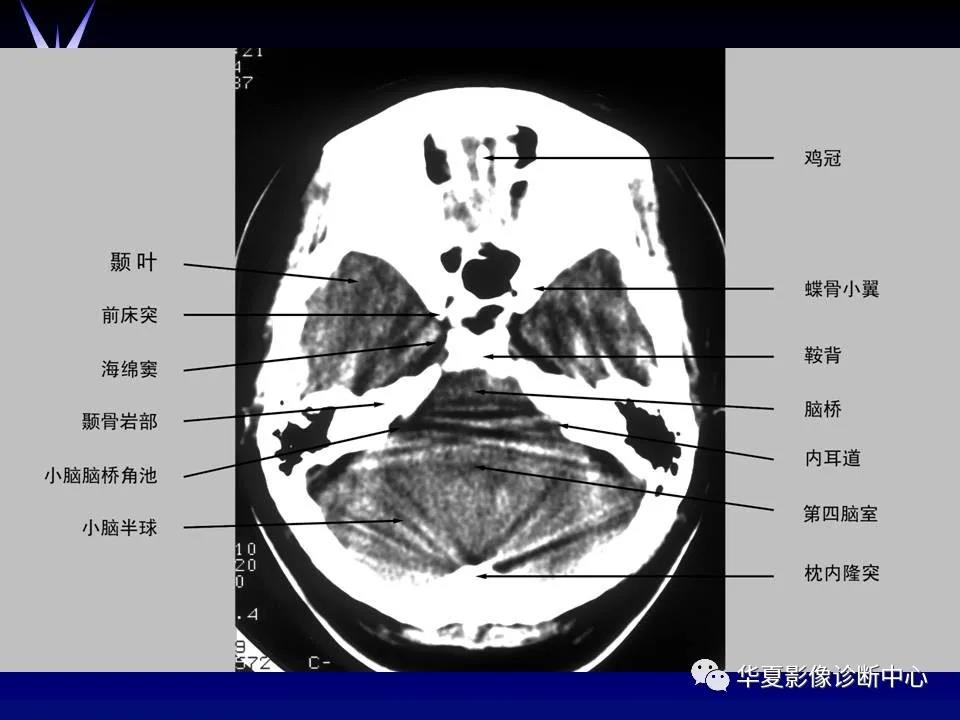

来源:华夏影像诊断中心